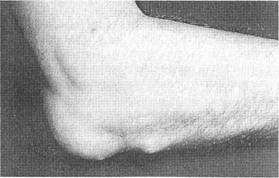

В области разгибательной поверхности локтевого сустава у 30% больных ревматоидным артритом можно обнаружить ревматоидные узелки (рис.5). Они могут разрушаться с образованием кист и инфицироваться. Ревматоидные узелки могут образовываться и в других местах, подвергаемых давлению, таких, как затылок, ладони, крестец, ахилловы сухожилия.

Припухлость и болезненность в области локтевого отростка могут быть проявлением воспаления суставной сумки, выстланной синовией и продуцирующей синовиальную жидкость (см. рис.5). Локтевой бурсит может осложниться разрывом сухожилий и инфицированием.

Рис.5. Локтевой бурсит и ревматоидный узелок